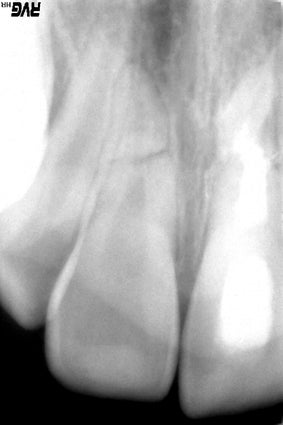

Op de röntgenfoto is de breuk van de wortels te zien.